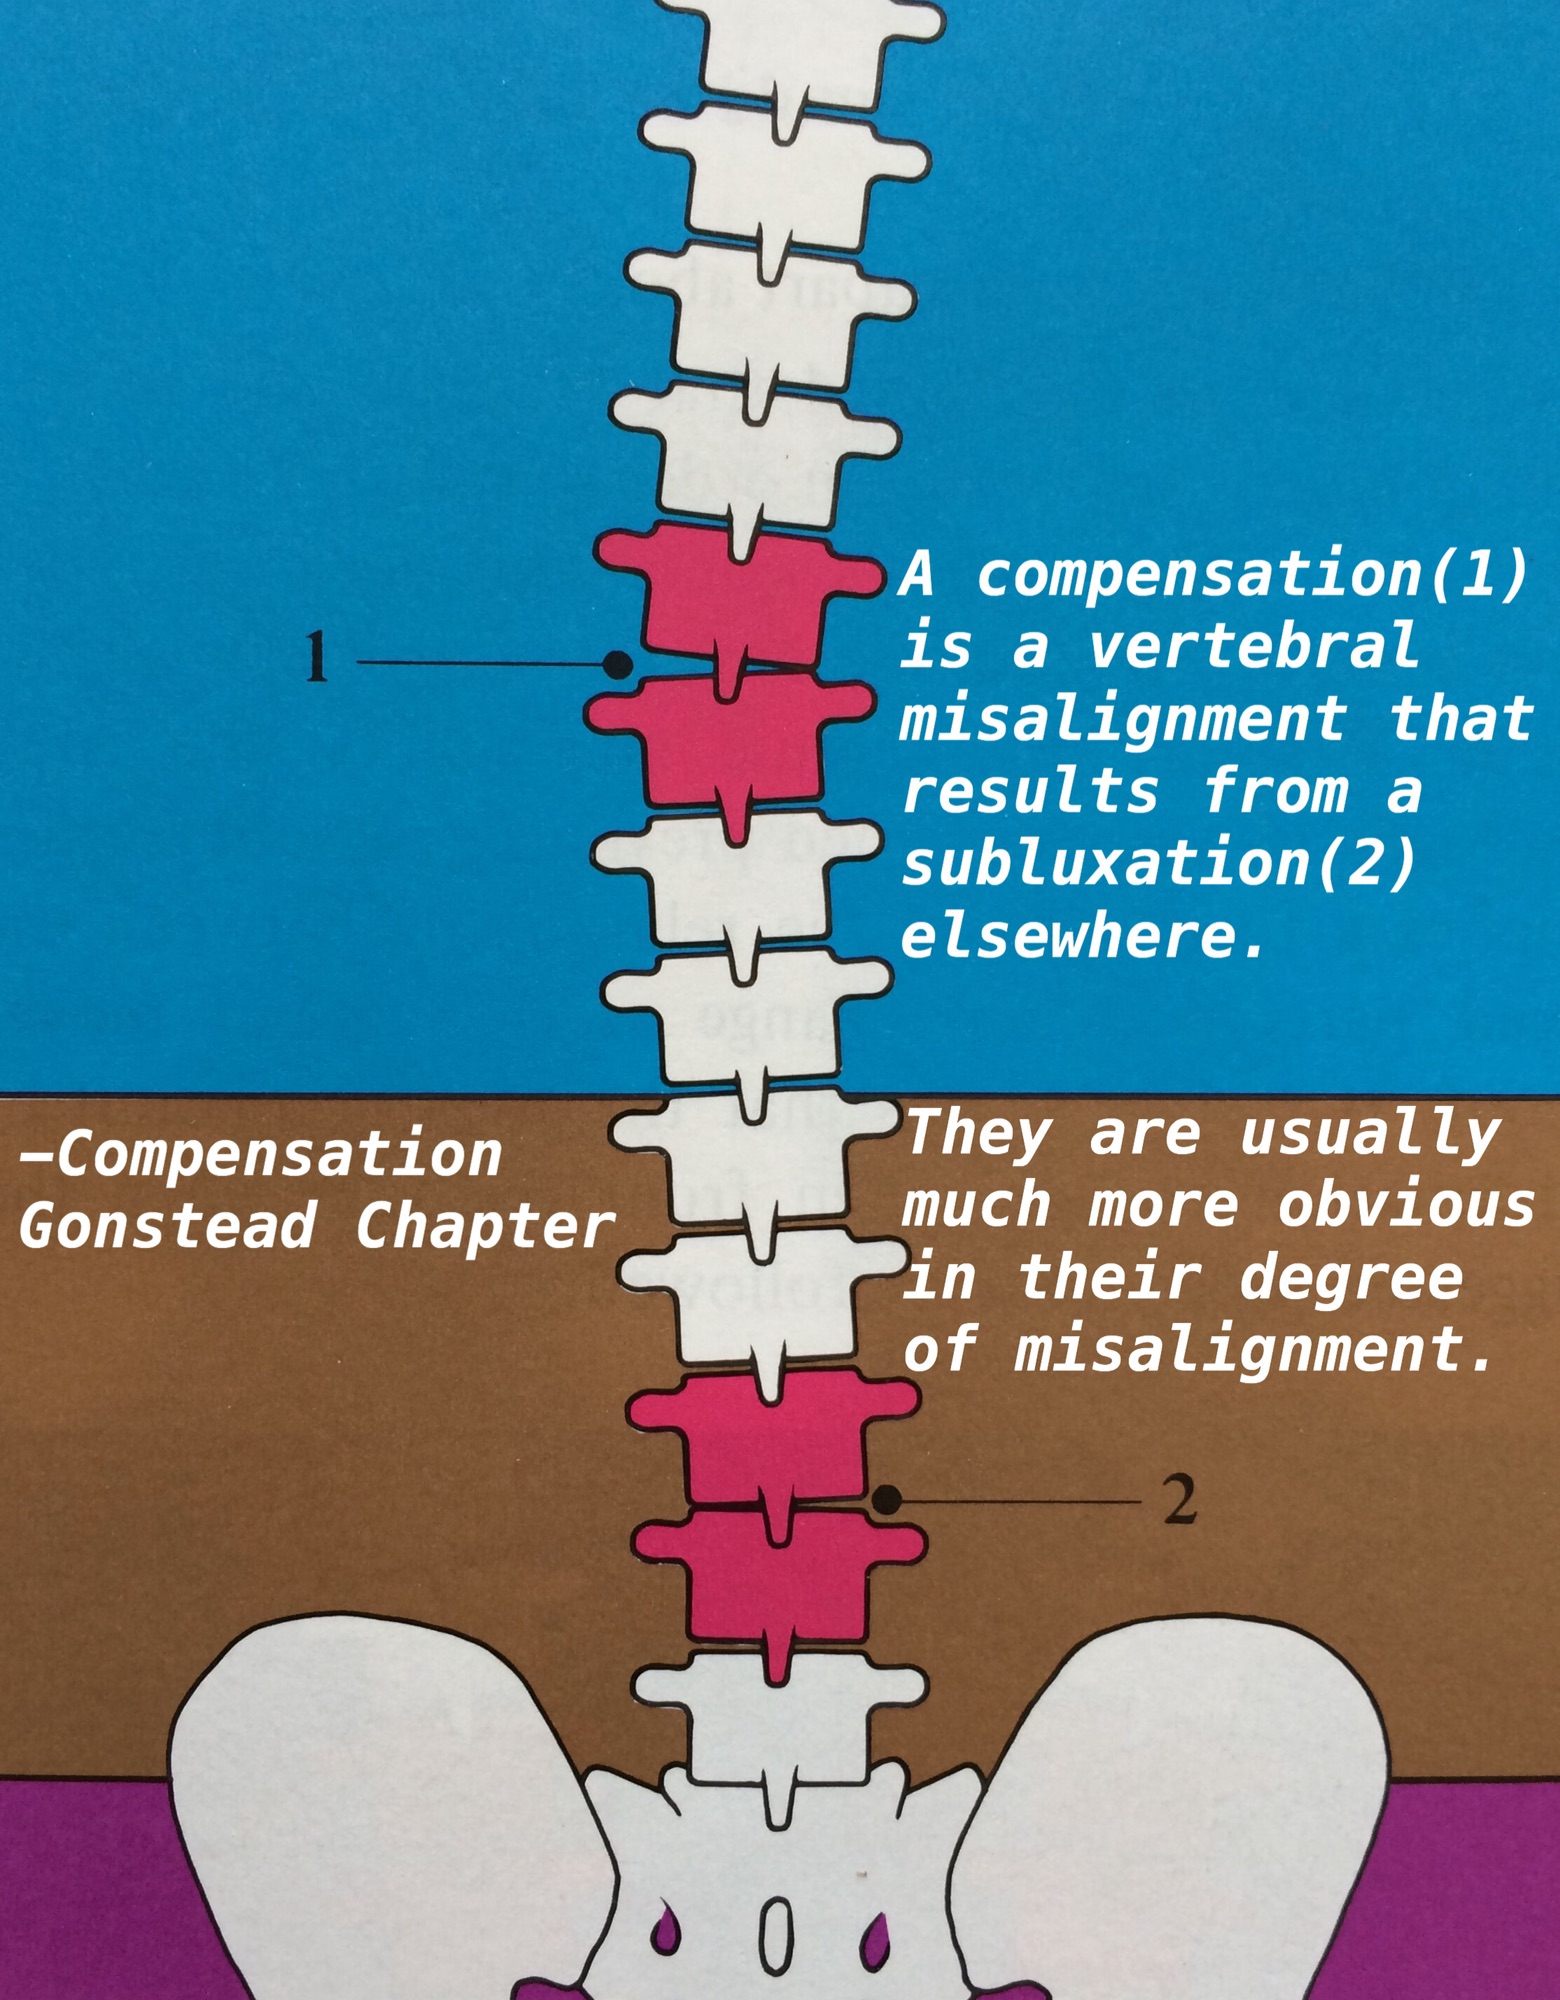

Compensation

Compensation

1番悪そうに見えても、そうとは限らない

1番悪そうに見えても、そうとは限らない